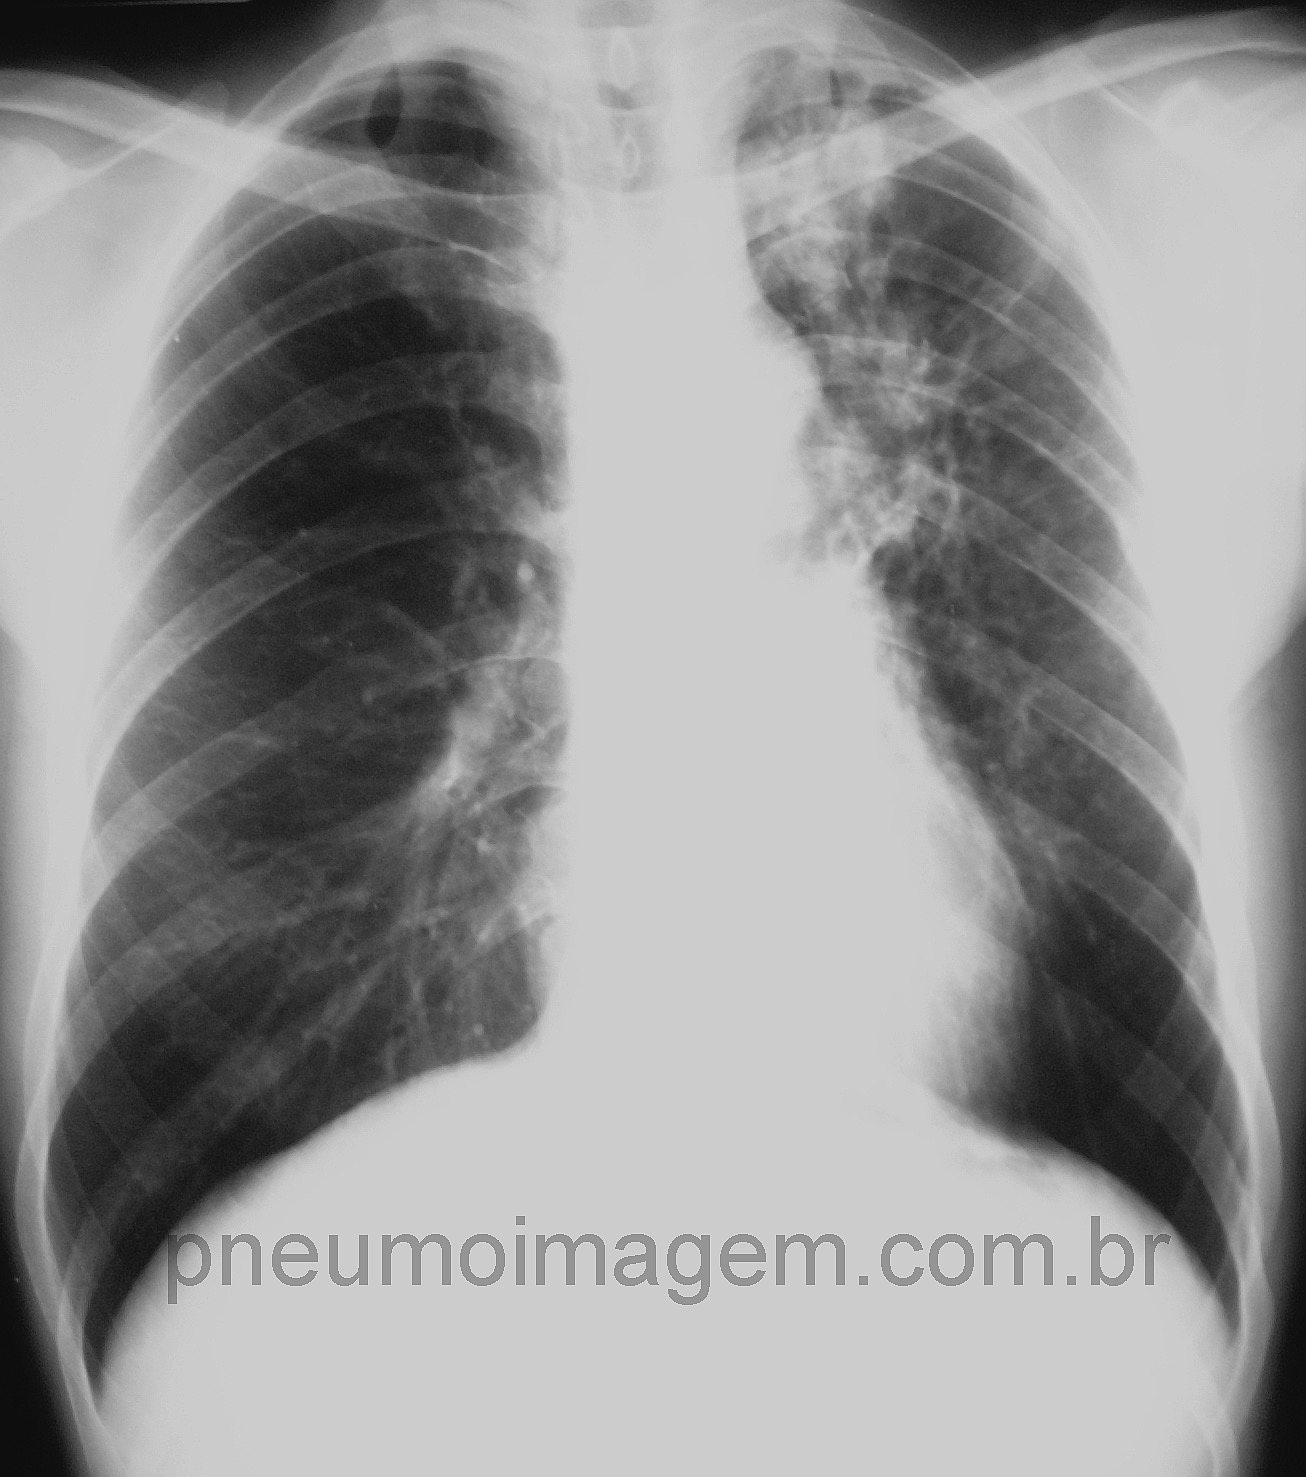

CASO CLÍNICO #19Paciente com tosse persistente há um mês, febre e sudorese noturnas e perda do apetite. Qual o diagnóstico? Deixe seus comentários abaixo.

Patient with persistent cough for a month, fever and night sweats and loss of appetite. What is the diagnosis? Leave your comment below.